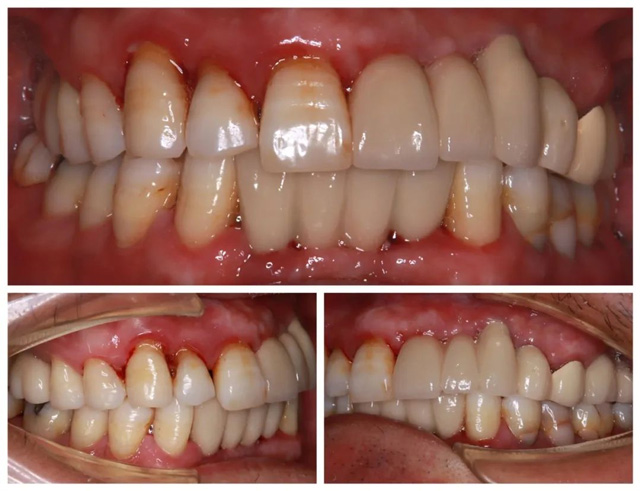

經(jīng)CBCT全景檢查所見(jiàn),謝海洋主任發(fā)現(xiàn)卞先生存在多顆牙缺失、殘存牙體伴有嚴(yán)重骨吸收,且多顆修復(fù)體失效等問(wèn)題,亟待通過(guò)種植牙重建咬合功能。針對(duì)顧客異地就醫(yī)、就診時(shí)間有限的情況,謝海洋主任為卞先生制定了“上下頜多顆即拔即種+連冠修復(fù)”的個(gè)性化種植方案:下頜種植2顆基牙支撐2顆連冠,上頜右側(cè)種植2顆獨(dú)立基牙,上頜前側(cè)種植3顆基牙連冠修復(fù)1顆。

為確保治療的質(zhì)量與效率,醫(yī)院特別開(kāi)通綠色通道,協(xié)調(diào)種植體供應(yīng)商優(yōu)先供貨,各科室無(wú)縫銜接診療環(huán)節(jié)。術(shù)后卞先生順利佩戴隱形義齒過(guò)渡,考慮到其工作休假的特殊性,醫(yī)院根據(jù)卞先生的安排,貼心將正式牙冠安裝時(shí)間延至2025年1月。

“原本擔(dān)心異地就診麻煩,沒(méi)想到每個(gè)環(huán)節(jié)都安排得井井有條。從接診到治療全程高效專(zhuān)業(yè),這種真正為患者著想的服務(wù)太難得了!”卞先生表示,“從1月份佩戴完正式牙冠到現(xiàn)在,我是吃嘛嘛香!”